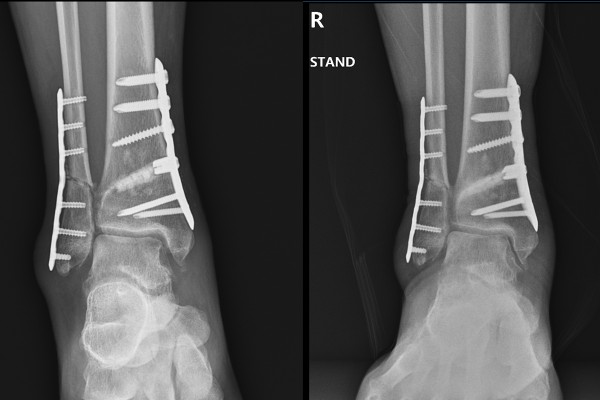

촬영한 발목 X-RAY에서 발목 관절의 공간이 확인되는 좌측 발목에 비해, 우측 발목 관절의 경우 공간이 없는 것을 확인하여 우측 발목 관절염 (Takakura stage 3B)(OA ankel Rt.(Takakura stage IIIB))을 진단하였습니다.

환자분께 현재 발목 상태와 수술적 치료의 필요성을 설명드렸고, 우측 발목 과상부 절골술(Rt. ankle A/S + SMO(supramalleolar osteotomy) + fibula shortening + Deltoid resection + open MBO)을 시행하였습니다.

수술 후 X-RAY에서 잘 고정되었고, 발목 안쪽의 공간이 생긴 것이 확인됩니다.

수술 전/후 X-RAY를 비교해보면 더욱 확실하게 알 수 있습니다.